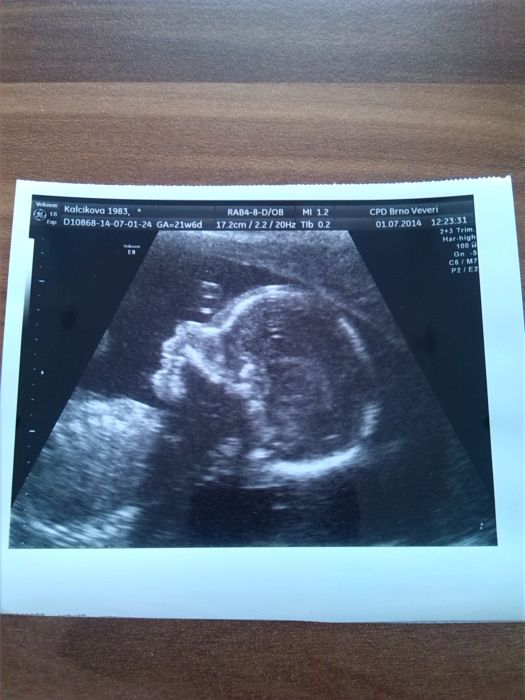

A tady jedno foto

Renatko, to je dobre, ze ti cukr taky dopadl dobre. Ty jo, to jsi uz daleko, taky se na ten dalsi ultrazvuk uz tesim, ja si ale jeste mesic musim pockat :-(. Fotecka krasna, to uz je krasnej clovicek :-)

Povedena fotka Ren,je to rozdil,proti tem fazolkam ze zacatku :-) Me ceka v patek ten 4D,tak se tesime:-) Obcas vzpominam na holky,kterym to nevyslo. Ty uz se budou moct pomalu zas snazit. Tak doufam,ze nam sem brzo napisou. Jinak co tady ctu a cte se to moc dobre,ze srdicka v poracku,cysty pryc,kontroly v poradku :-) Moc nam vsem drzim pesti!